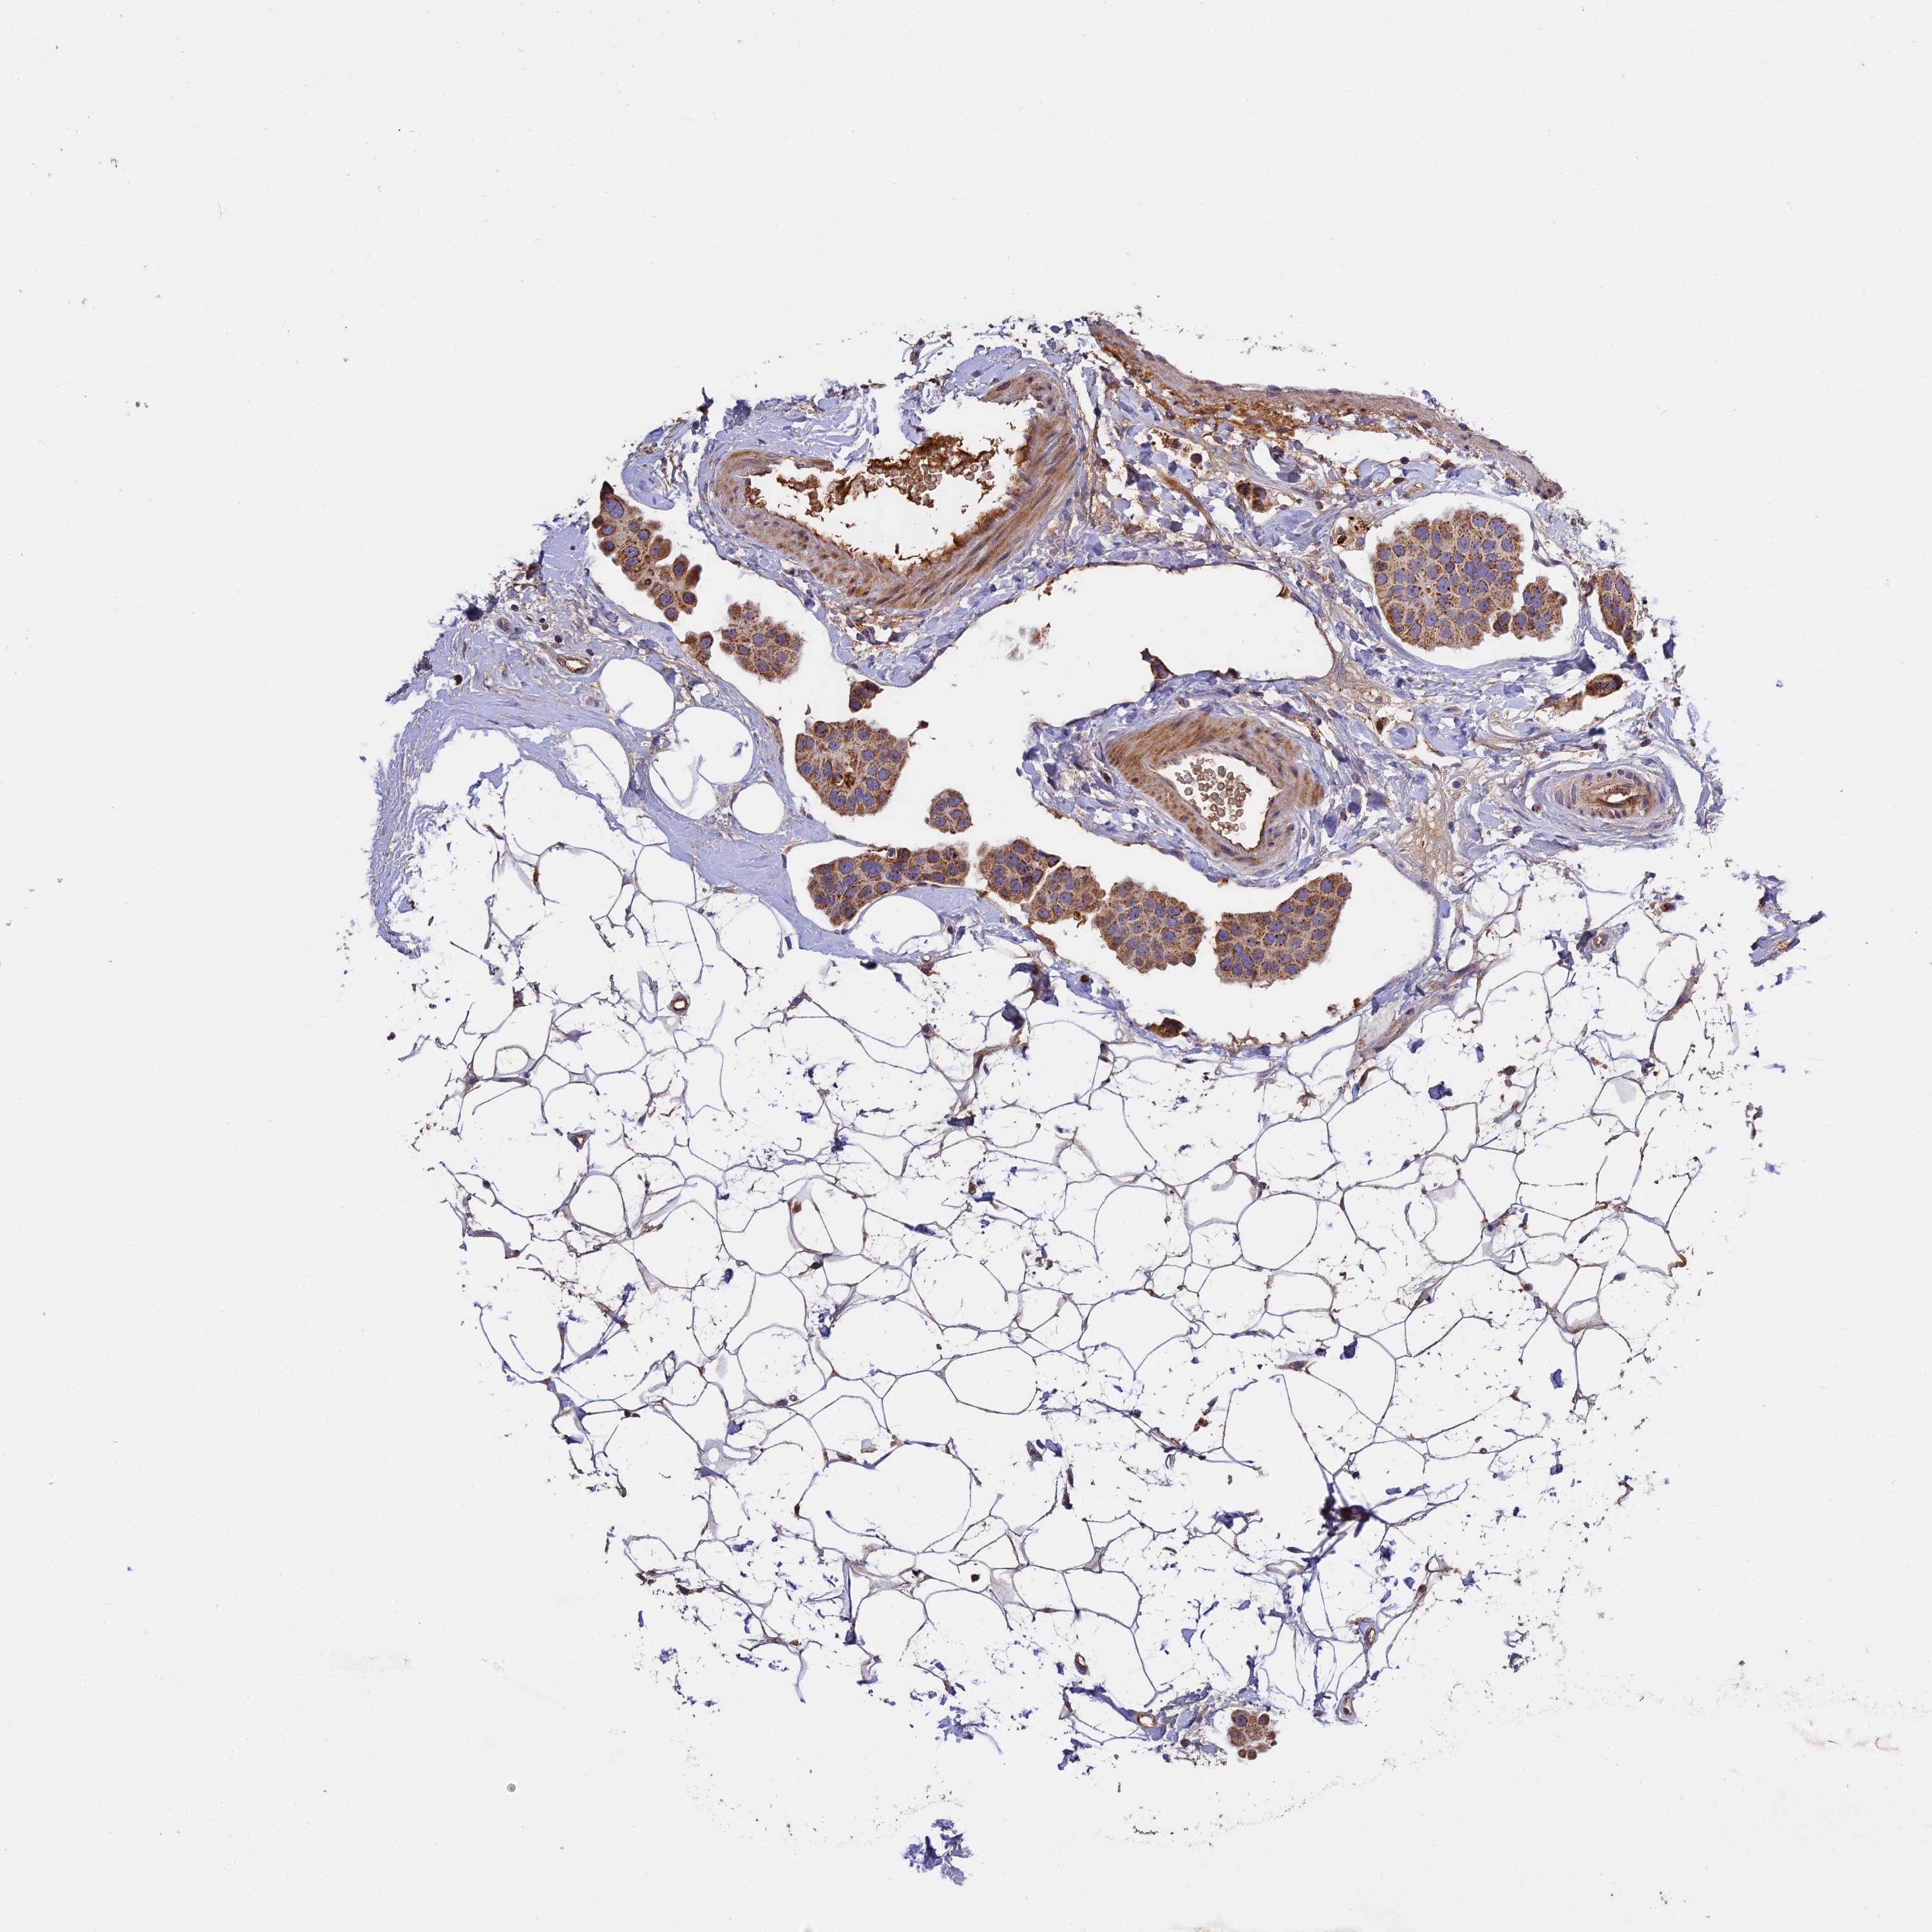

CANCER BREAST CANCER Show tissue menu

BRCA TCGA BRCA VALIDATION PROTEIN EXPRESSION